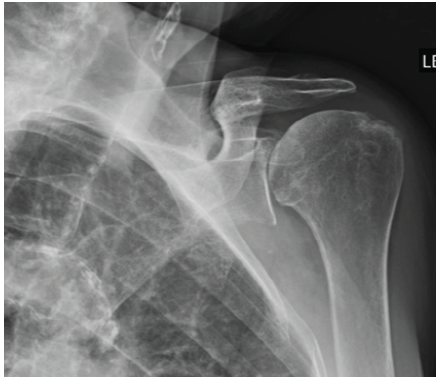

Warfarin-associated Spontaneous Hemorrhage from the Lateral Pectoral Artery after Reverse Total Shoulder Arthroplasty: A Case Report

Hayley E Hansen , Lucas Haase , J Michael Wiater